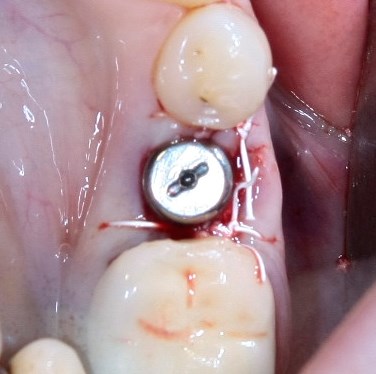

Немедленная имплантация — оптимальное решение в любой клинической ситуации